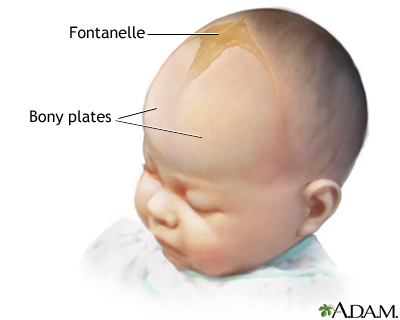

what are fonatelles? why do they exist?

Babies have much wider/expansive sutures: fonatelles

- anterior fontanelle found between two parts of frontal bone.

- this helps with post-natal growth of the skull and allows the brain to grow/expand, and also helps head deformity during birth. Can measure intercranial pressure, will bulge if pressure in skull has increased

what are fonatelles? why do they exist?

Babies have much wider/expansive sutures: fonatelles

- anterior fontanelle found between two parts of frontal bone.

- this helps with post-natal growth of the skull and allows the brain to grow/expand, and also helps head deformity during birth. Can measure intercranial pressure, will bulge if pressure in skull has increased